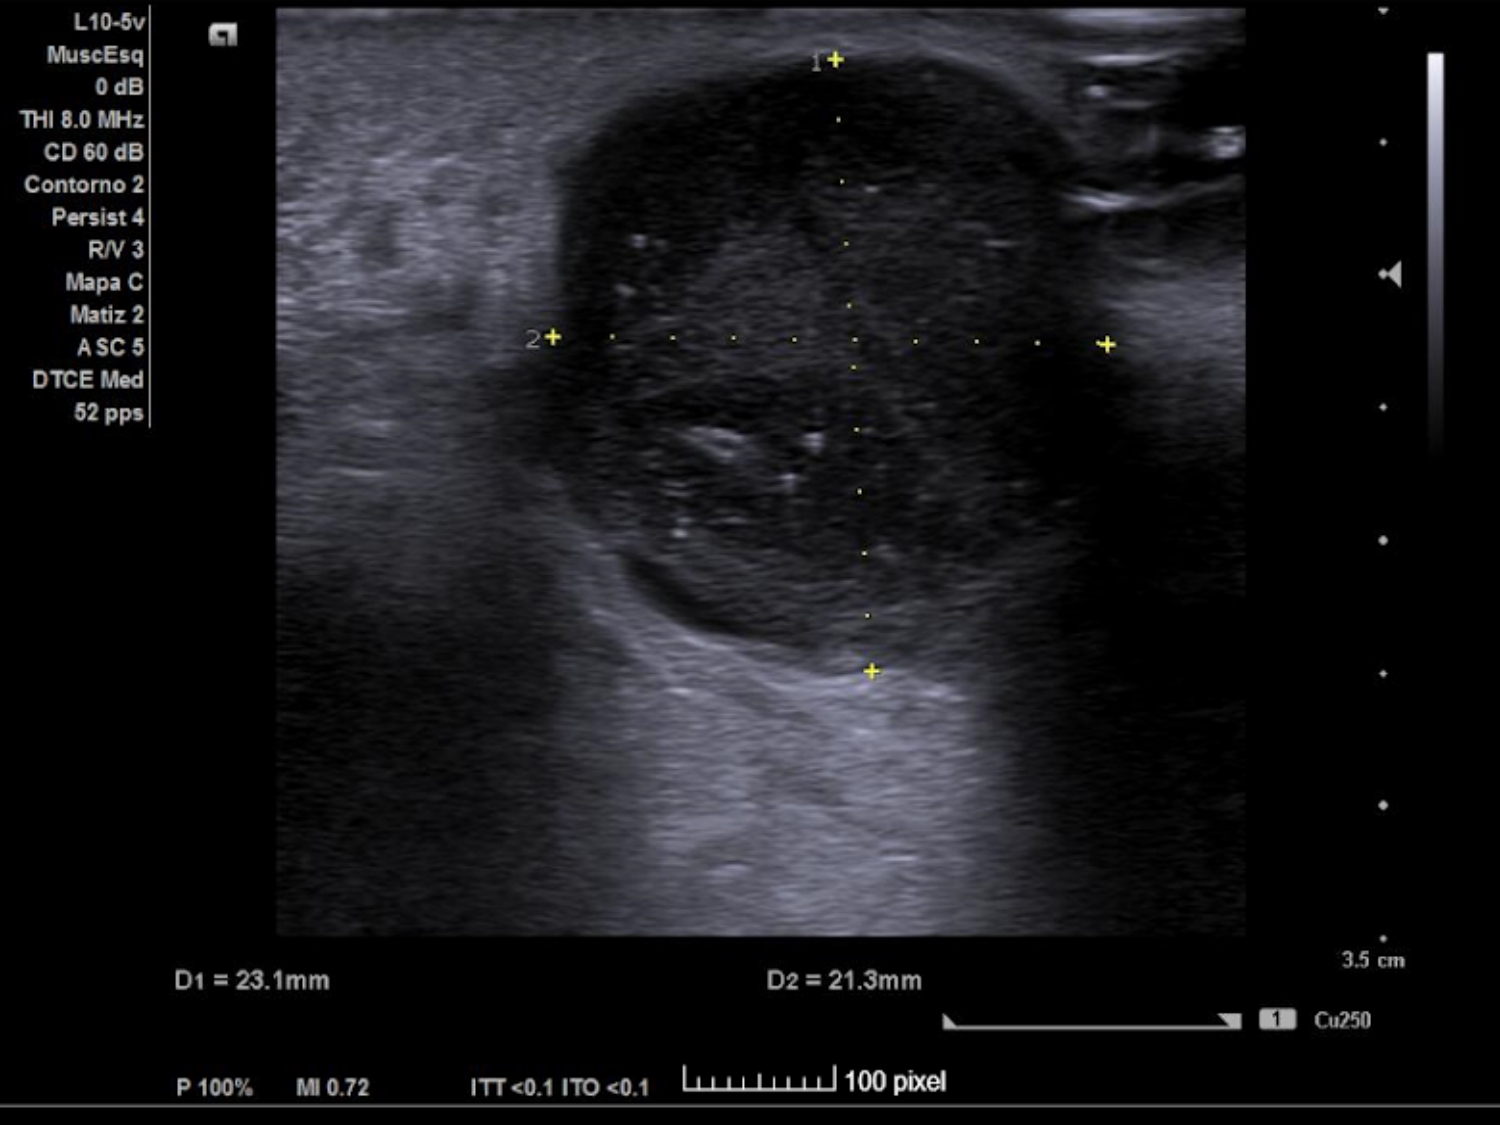

Se realiza ECO POCUS en la que se aprecia un absceso de 23 x 21 mm a menos de 1 cm de profundidad, con fácil acceso a nivel cutáneo y contenido heterogéneo, más anecoico en algunas zonas y poco tabicado.